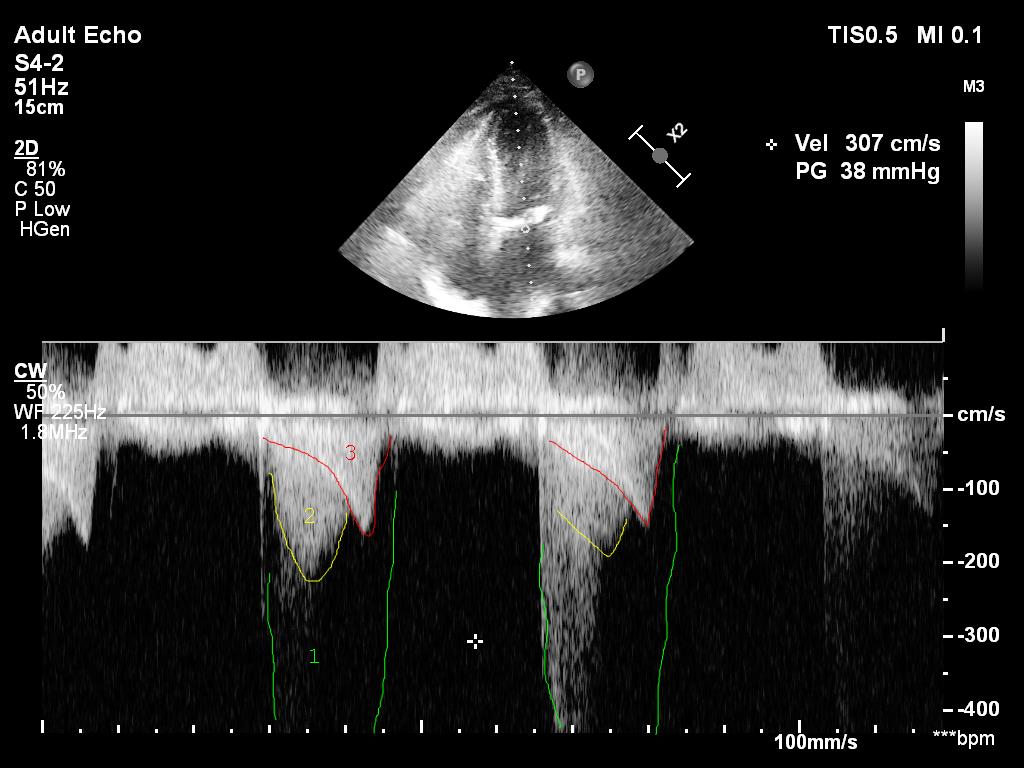

2/ I cheated. This is actually a pic after an intervention. This was the original.

A4C

13/ On this earlier pic the intraventricular peak gradient (red late peaking, saber like) is 43hgmm. It is considered 'obstruction' if PG is above 30hgmm and hemodynamically significant if above 50hgmm. This one here is clearly an issue.

Is there aortic stenosis too though?

14/ If I just look at the mean gradient on the previous clip (34hgmm), there is. However, it is impossible to calculate the true gradient if there is an intraventricular obstruction.

After starting vasopressin with 2U/h noradrenaline could be reduced and intraventricular obstruction improved from 43hgmm to 9 hgmm. Urine output picked up. Pt was discharged 2 days later.

Intraventricular obstruction almost disappeared...

23/ Mean aortic gradient was only 17hgmm (reduction from 34). This corresponds to NO aortic stenosis (cutoff 20hgmm, Vmax 2.5m/s) and I reported it as aortic sclerosis.